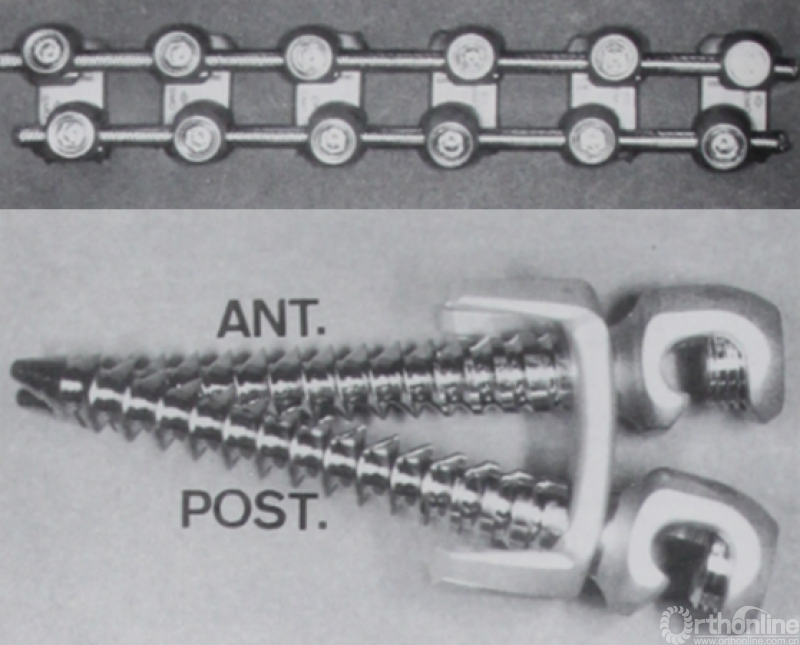

1996年Kaneda等人[3]提出的双棒技术通过两颗椎体螺钉来固定每个节段。这在椎体上创造了一个非常强大的三角形抓持力,可以对脊柱弯曲施加更强有力的矫正。临床结果显示,脊柱侧凸矫正效果显著、立体、稳定。

图2.脊柱侧凸前路双棒内固定系统

内固定选择的是5.5mm双棒系统,先置入顶椎的螺钉垫板。

置入顶椎的椎体螺钉,螺钉可置入椎体中部到后方1/3之间的范围内。

使用双棒系统时,先置入背侧的螺钉,螺钉指向椎体中线,后置入腹侧的螺钉,螺钉轻度指向后侧。形成对椎体的三角形抓持力。